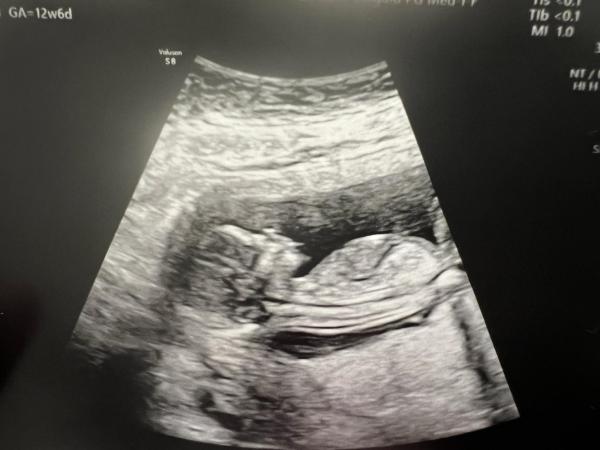

Hallo ihr lieben ich hatte heute mein ETS, das Baby hat sich fleissig bewegt😍. Bin heute 12+6, meine Ärtzin meinte bzgl dem Geschlecht ist es noch viel zu früh. Trotzdem bin ich extrem neugierig, habe jetzt so oft von der Nub Theorie gehört, ob das wirklich stimmt ist so eine Sache. Aber aus Neugier würde ich mal gerne hören was ihr denkt. Habe in 4 Wochen wieder einen Termin wäre dann interessant, ob das geratene dann damit übereinstimmt.